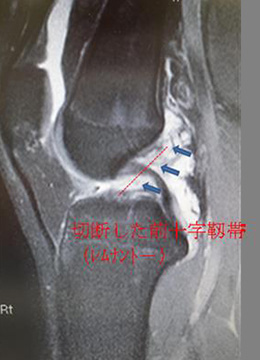

自分の組織を用いて再建する(自家腱移植)のがベストな方法とされています。当院で行っている膝屈筋腱(ハムストリングス)を用いた関節鏡視下膝前十字靱帯再建術は、切開は最小限で大きな合併症がなく、術後の成績も安定しているため、有効な治療方法として確立されています。 手術は膝関節を構成する大腿骨と脛骨の最適部位に関節鏡を用いて細いトンネルを作製し、そこに採取加工した腱を貫いて上端と下端を金具で固定することで膝の安定性を得ることを目的とし、全身麻酔+硬膜外持続麻酔下で行います。尚、本院では遺残靱帯(レムナント)が残存している患者様に対しては再生医療の観点※からレムナントを切除せずレムナントを利用し一重束前十字靱帯再建術(レムナント温存法)を、また女性で膝が柔らかい患者様(反張膝の患者様)などには二重束前十字靱帯再建術を、また二度目の受傷の患者様などには膝蓋腱を用いて一重束前十字靱帯再建術(BTB法)をおこなっています。また、縫合可能な半月板損傷がある患者様に対しては全例半月板縫合を行います。(Biomet MaxFire™ を利用し、関節内だけの操作で縫合します。)手術時間はレムナント温存法で行った時は約1時間から1時間半です。